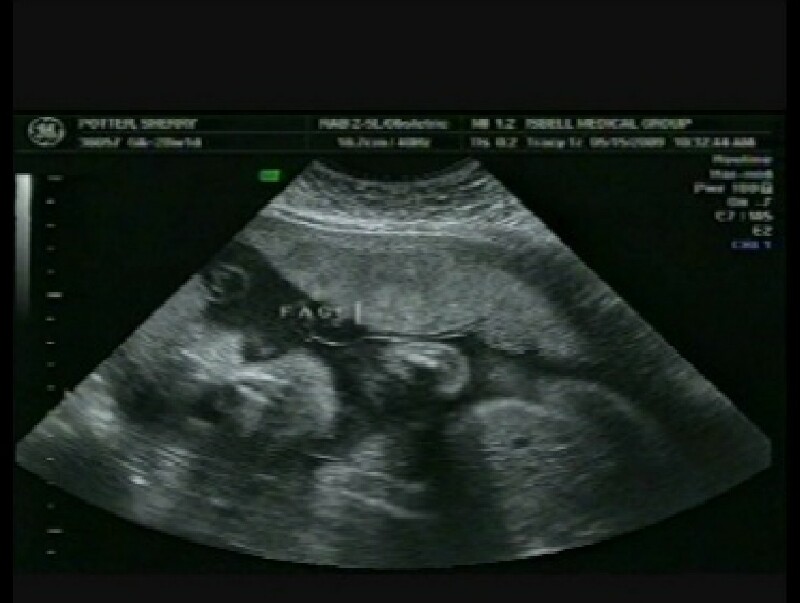

Hayley Grace May 15, 2009